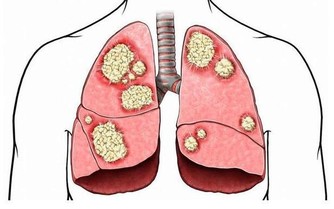

肝臟是人體內重要的新陳代謝器官,因為現代人的生活不規律、飲食不健康導致肝臟內積存了大量毒素。進而導致肝功能下降,體內新陳代謝出問題,久而久之,肝臟很容易患疾病,嚴重甚至導致肝硬化、肝癌。然而大部分肝病並沒有明顯症狀,是真正的「隱形殺手」,所以要做到防患於未然,從改變飲食規律和日常習慣做起。